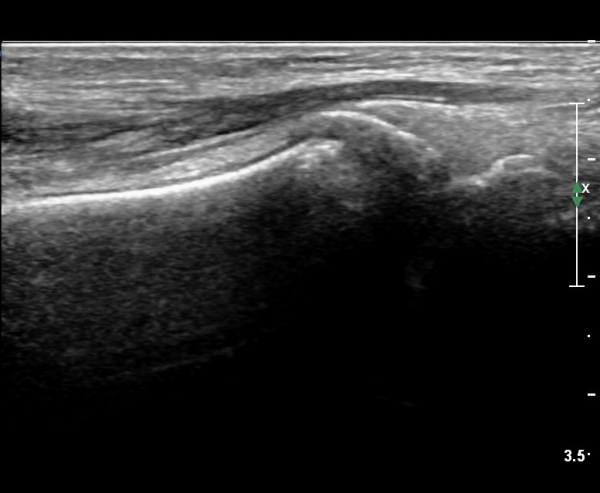

ÃÊÀ½ÆÄ °Ë»ç

CT : avulsion fracture of distal tibia at distal tibiofibulat ligament insertion.